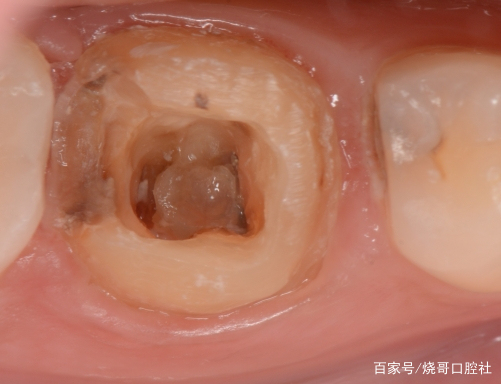

3、牙齒變色:牙洞深入牙髓后,可能會導(dǎo)致牙齒顏色發(fā)生變化,如牙齒變黑或變黃。

1、口腔鏡檢查:通過口腔鏡檢查,可以清晰地觀察到牙齒表面的牙洞以及牙洞內(nèi)的情況,醫(yī)生可以判斷牙洞是否已深入牙髓,并評估病情嚴(yán)重程度。